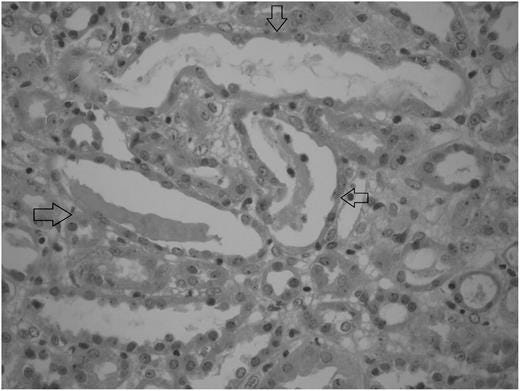

But dysfunctions can happen even at low doses of supplementation. In a 2011 case study, Taner et al. reported a healthy 18-year-old man who presented with a 2-day history of nausea, vomiting and stomach ache while taking creatine monohydrate for bodybuilding purposes. The patient had acute renal failure, and a renal biopsy was performed to determine the cause of increased creatinine and proteinuria. The biopsy (shown above) showed acute tubular necrosis. In the literature, creatine monohydrate supplementation and acute tubular necrosis coexistence had not been reported previously. Twenty-five days after stopping the creatine supplements, the patient recovered fully. The authors conclude “Even recommended doses of creatine monohydrate supplementation may cause kidney damage; therefore, anybody using this supplement should be warned about this possible side effect, and their renal functions should be monitored regularly.”